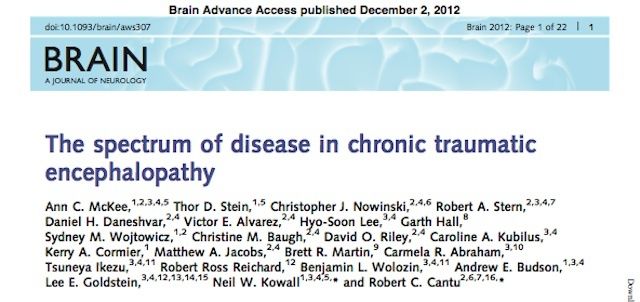

A recent scientific study, published in the journal Brain in December, bolstered the link between repeated concussions and mild traumatic brain injury. The study examined the brains of 85 people, 68 of them (80%) men, including 33 former NFL players and 17 non-NFL football players. The study was the first to categorize the stages and progression of the disease, but it wasn’t able to conclusively demonstrate a link between C.T.E. and on-field injuries. Nor was it able to predict the risk NFL players have for developing the disorder nor explain why some players develop it while other don’t.